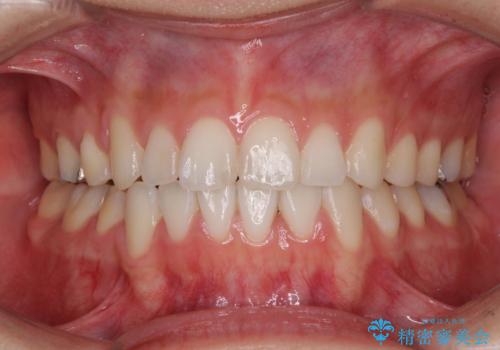

- 前歯のデコボコと若干口元が突出していることを気にして来院された患者様です。

全体的に軽微な叢生が認められ、口元もやや前方に突出していたため、インビザラインでのIPR(歯と歯の間を削る)と歯列全体の後方移動によって歯並びを整えることとしました。

上下ともに歯列の幅が狭かったため、側方に拡大することで前歯のデコボコや突出感を解消するためのスペースを獲得することができました。

歯並びが改善したことはもちろん、咬み合わせの改善まで実感することができ、患者様には大変満足していただけました。